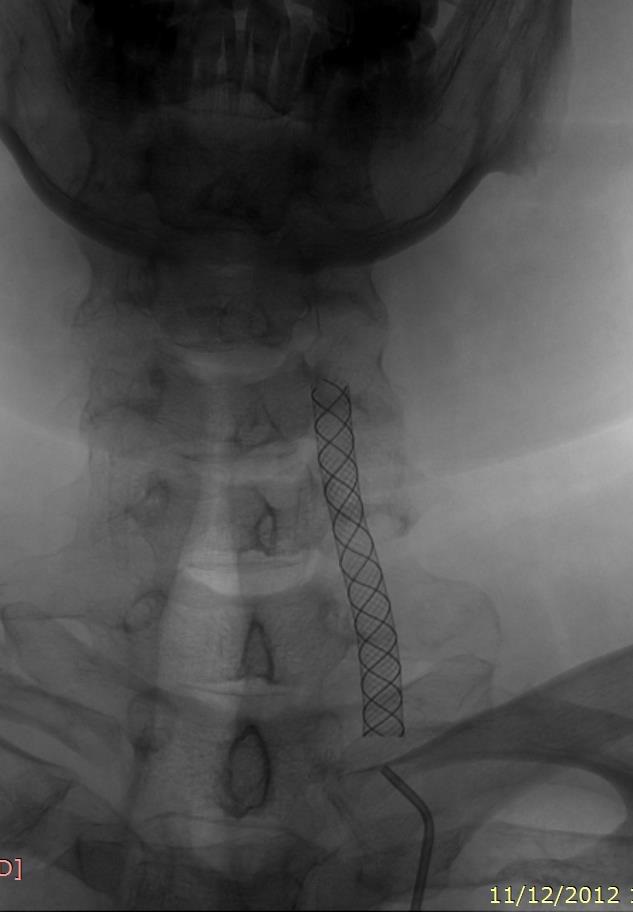

Parking back door-front door stent graft

6mmX60mm wallgraft

residual filling decrease by time but persist till 30 min after stenting

Good stent-graft placement